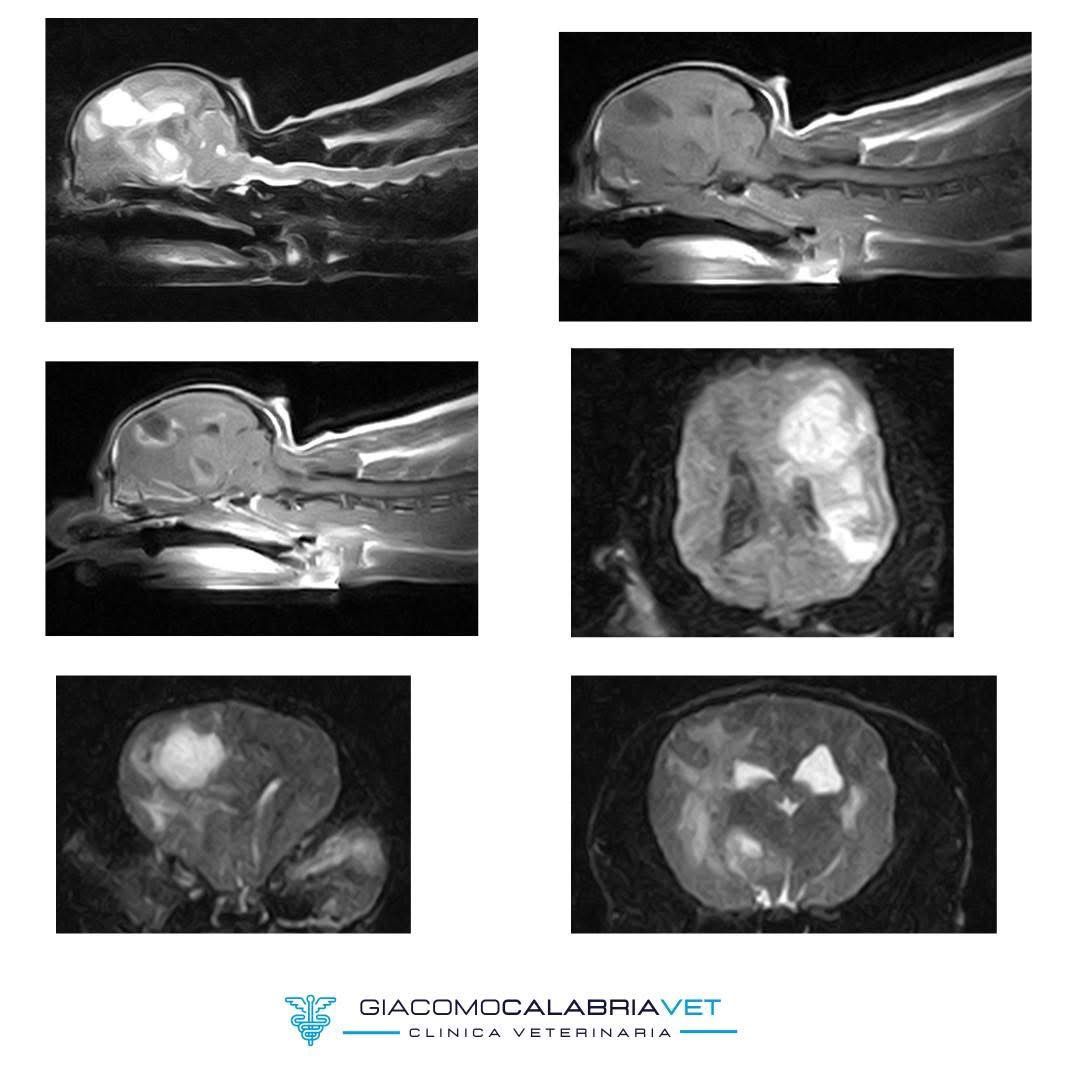

RISONANZA MAGNETICA